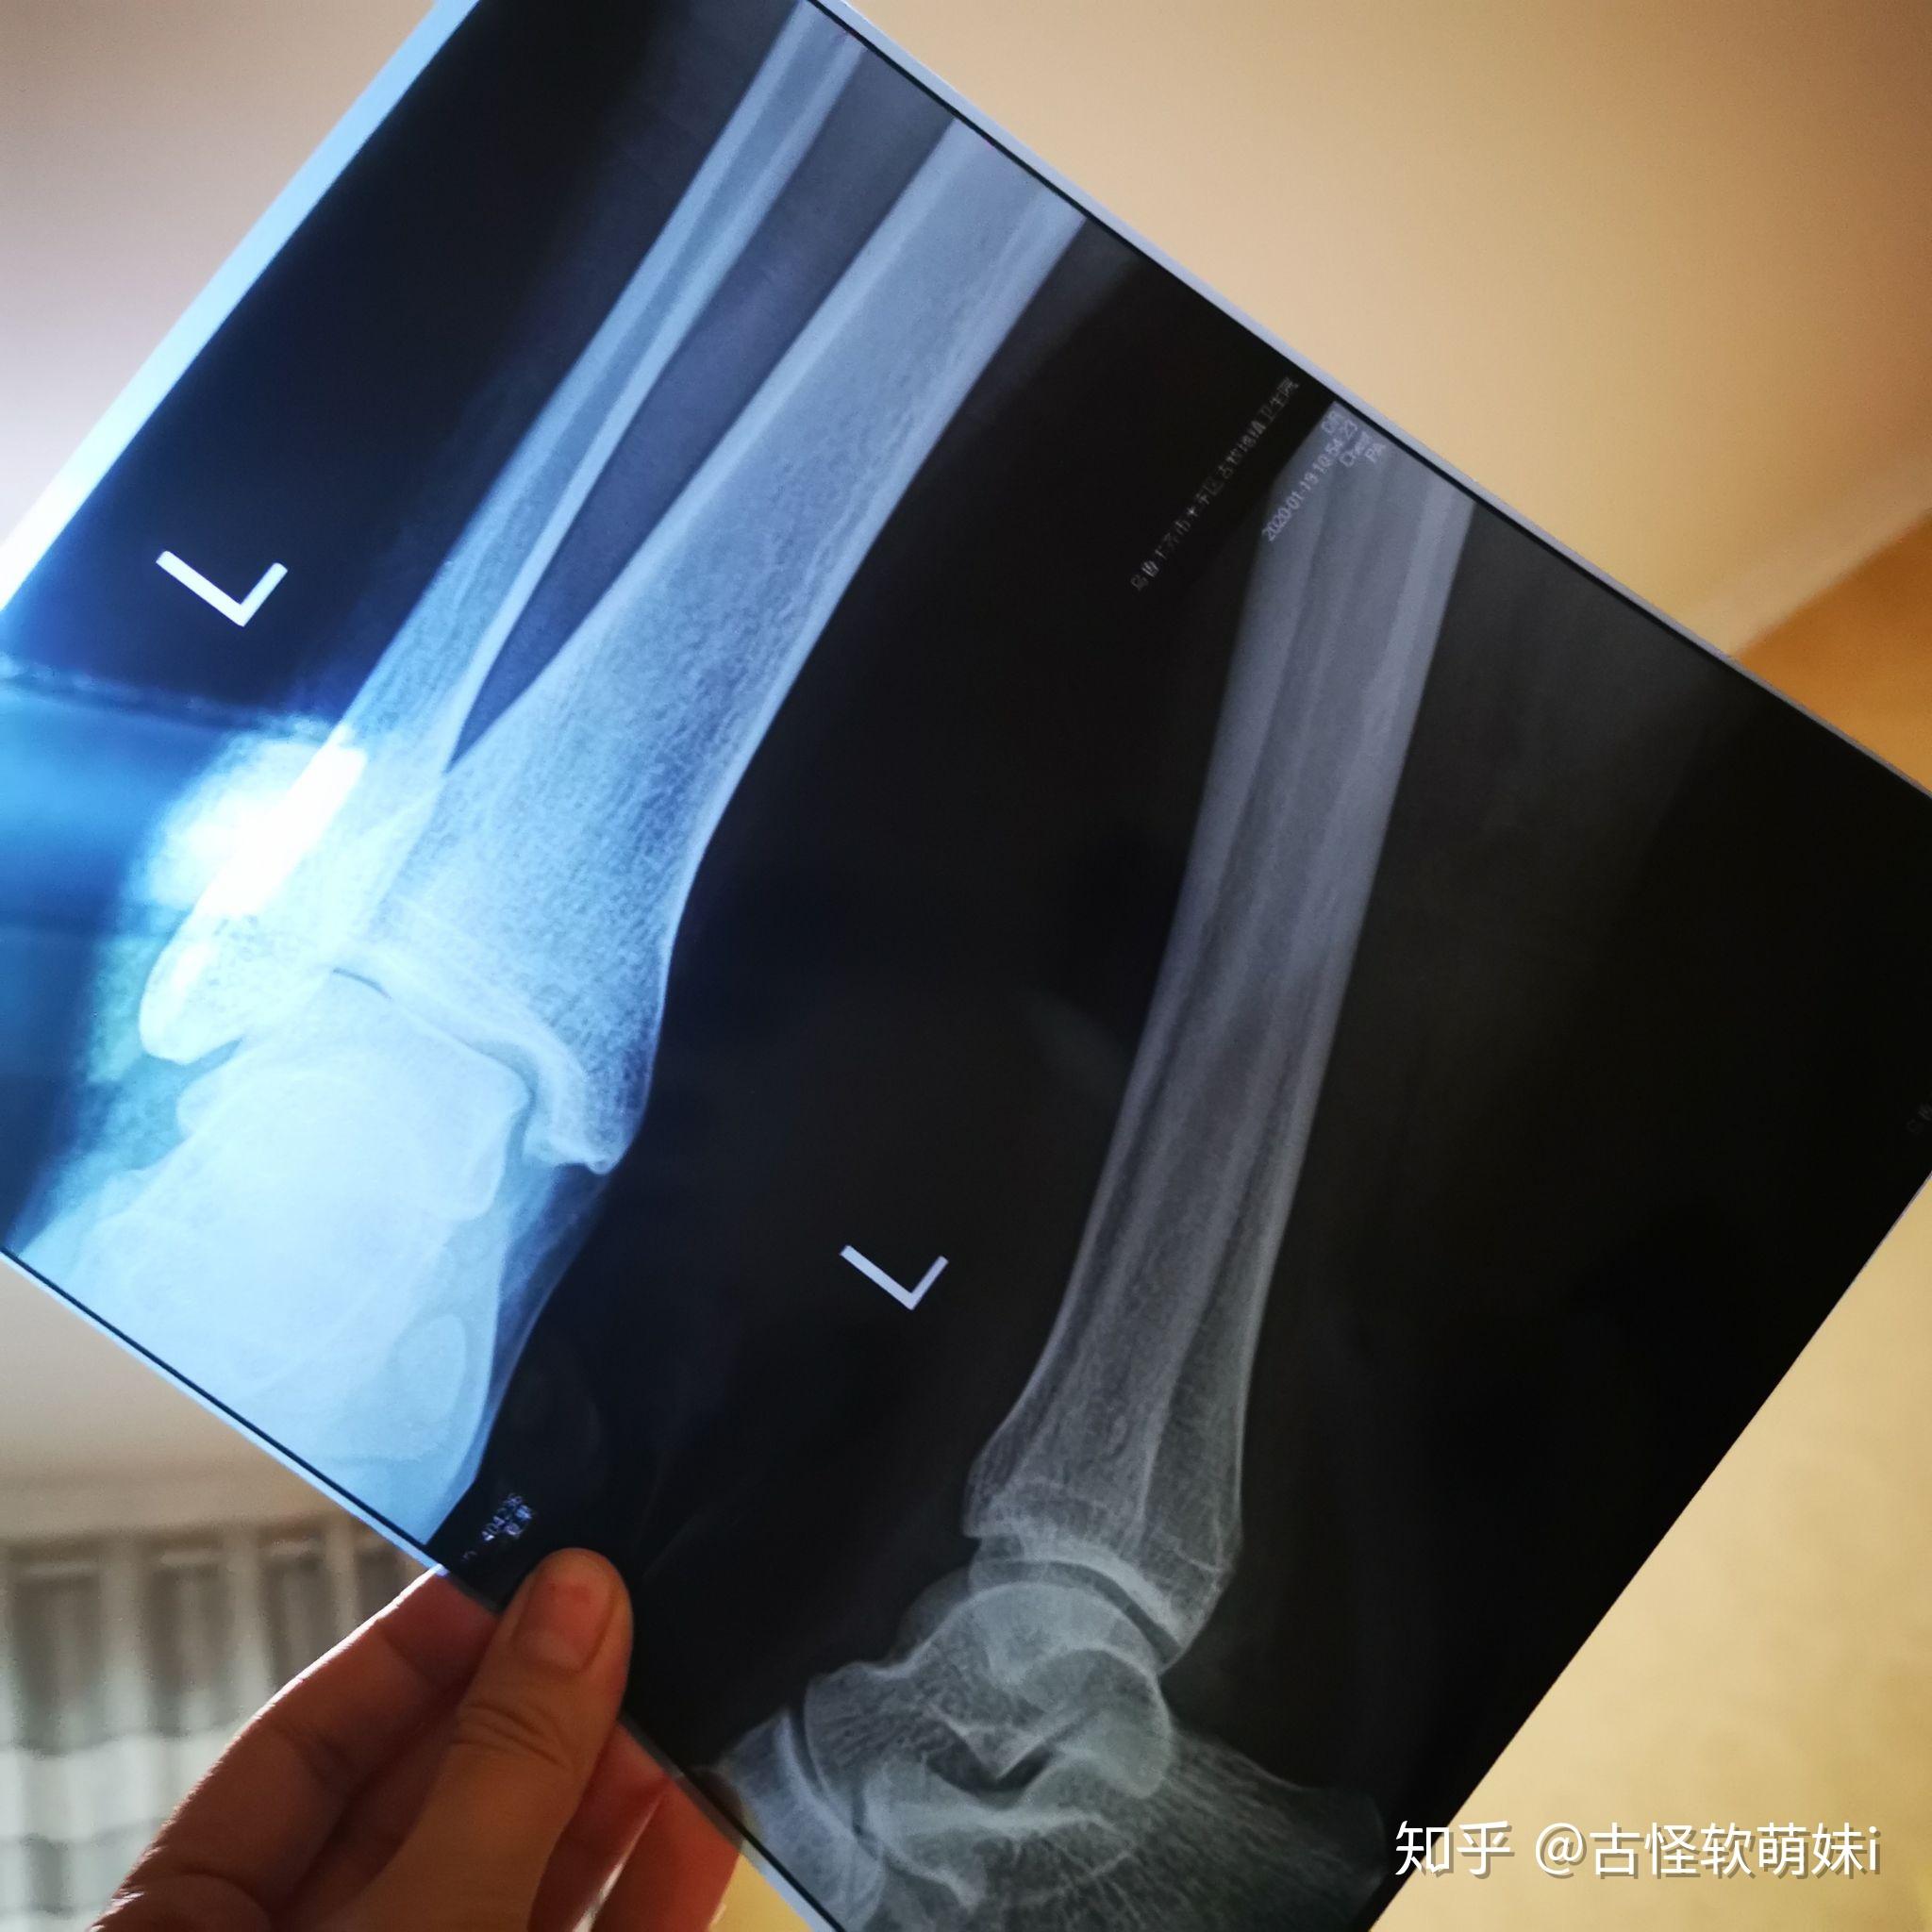

左外踝骨折

正位显示外踝骨折移位,造成踝关节不稳